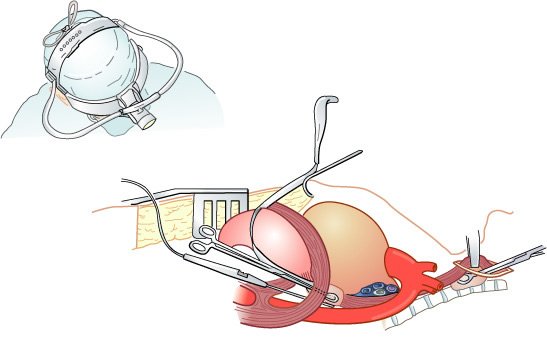

Mobilização esofágica durante esofagectomia transiatal sob visualização direta, auxiliada pela ampliação do hiato diafragmático e retração anterior das estruturas mesomediastinais Piloromiotomia e jejunostomia alimentar são realizadas de rotina. Todo o esôfago torácico, do nível das clavículas à cárdia, é ressecado, enquanto há monitoração cuidadosa da pressão intra-arterial para evitar hipotensão prolongada pela mobilização cardíaca durante a dissecção esofágica transiatal .

Para tumores do terço proximal do esôfago, a adição de uma secção parcial do esterno facilita a dissecção do esôfago da traquéia sob visualização direta.

Os críticos da esofagectomia transiatal argumentam que a exposição do esôfago torácico é limitada através do hiato. Este fato potencializa o risco de hemorragia incontrolável pela lesão da veia ázigos, das veias pulmonares e do arco aórtico, e não contempla a dissecção ganglionar completa para estadiamento e cura potencial.

Enquanto a esofagectomia transiatal focaliza a redução da morbidade pós-operatória por evitar a toracotomia, a esofagectomia transtorácica permite completa dissecção ganglionar sob visualização direta da massa tumoral e dos tecidos adjacentes, com completo estadiamento do tumor e a possibilidade de maior morbidade peroperatória.

O esôfago repousa no lado direito do mediastino, exceto em seu terço distai, que se curva à esquerda. Além disso, o arco aórtico repousa sobre a lado esquerdo do esôfago proximal e obscurece a visualização durante a ressecção de um tumor do terço médio a superior.

A incisão de toracotomia póstero-lateral é realizada à direita, no quinto espaço intercostal, e à esquerda no sexto ou sétimo. A laparotomia mediana superior é realizada se o tumor encontra-se no terço superior do esôfago. A incisão cervical garante a exposição do esôfago cervical e da cricofaringe para obtenção de margem negativa.

O pulmão e o espaço pleural são examinados para a evidência de doença metastática.

- O ligamento pulmonar inferior é seccionado à veia pulmonar inferior.

- A área tumoral é examinada para evidência de invasão direta de estruturas mediastinais vitais.

- O esofago, os linfáticos periesofágicos e a pleura adjacente são ressecados, preferencialmente em bloco. Os linfonodos paratraqueais são removidos com o espécime primário.

- Tomando-se cuidado para evitar dano ou tração ao nervo laríngeo recorrente, há redução da disfonia.

- A veia ázigos e o ducto torácico são ressecados ao longo do espécime primário.

- A pleura oponente não é ressecada, a menos que pareça estar comprometida por tumor.

- O esofago é mobilizado do ligamento longitudinal anterior da coluna espinhal e, é então, seccionado 5 a 8 cm do EES, deixando-se uma distância suficiente do tumor primário (ao menos 5 cm, mas geralmente 10 cm) para evitar metástases salteadas ou disseminação linfática longitudinal